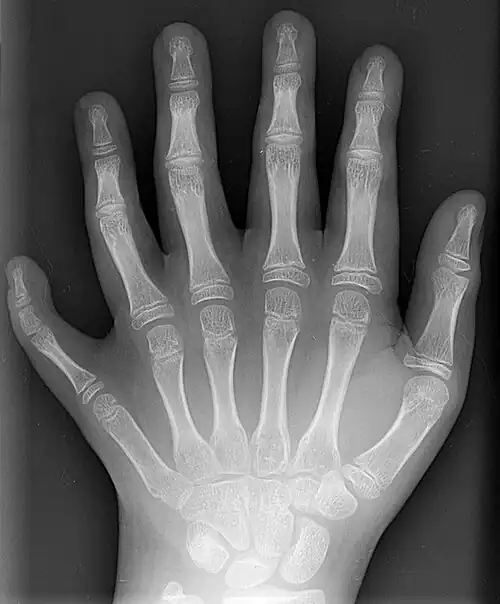

Classification is performed by using x-ray imaging to see the bone structures.[17] In 1961, Frantz and O'Rahilly proposed that congenital anomalies of the limb could be classified in seven categories, based on the embryonic failure causing the clinical presentation. These categories are failure of formation of parts, failure of differentiation, duplication, overgrowth, undergrowth, congenital constriction band syndrome, and generalized skeletal abnormalities.[36] In 1976 this was modified by Swanson.[37] Polydactyly belongs to the category of duplication.[12] As of 2009, research has shown that the majority of congenital anomalies occur during the 4-week embryologic period of rapid limb development.[12]

X-ray of type III central polydactyly. The middle fingers are the same length. -